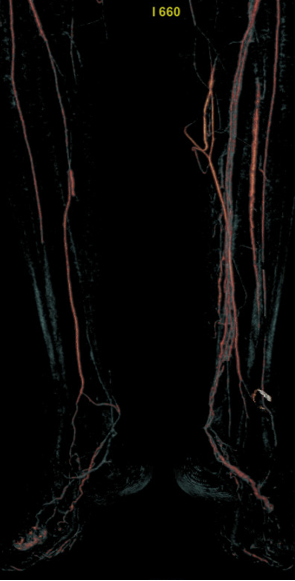

TAO动脉病变模式有 abrupt occlusion(突然闭塞)、Localized stenosis(局限性狭窄)、Moth-eaten stenosis(虫蚀样狭窄)等,还可能出现不规则侧支循环、侧支循环早期形成、树根样侧支、迂曲静脉等情况。

外科重建仅适用于10.2%患者,因远端弥漫性病变大多不可行

血管内治疗成为主要选择,尤其对于无远端旁路靶点患者

Buerger病的治疗核心是严格戒烟,血管内干预为当前主要手段,但长期预后仍依赖患者依从性及早期干预。